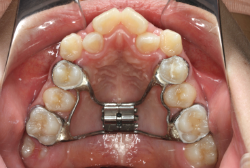

混合歯列期から治療開始した側方拡大による非抜歯症例

「配列の凸凹を治したい」という主訴で来院したケースです。診断の結果、永久歯がすべて生えそろうと、かなり厳しい叢生(歯並びの凸凹のことです)になる可能性が高いと判明しました。原因としては特に上の顎の骨が小さいため、歯を収容する容量不足になっていると診断しました。このケースの場合は、成長発育期に治療開始しますので、顎の骨を土台ごと大きくすることが可能です。

そこで、まず急速拡大装置を使用して上顎骨の拡大を行い、上顎骨の容量が拡大したことを確認後、マルチブラケット装置を使って全体の修正をする、と言う二段階の作戦をとることになりました。

この時期に使う急速拡大装置は、適切な診断に基づいて正しく使用することで確実に骨を大きくすることができます。拡大することで隙間が確保できるので、永久歯の抜歯を避けることができます。

急速拡大装置を1日1回装置の中央にある拡大ネジを、ご自身で回して頂くことで25日間くらいかけて、6mmほど拡大しました。拡大後は、上顎の前歯の隙間が広がっていることがお分かりいただけると思うのですが、土台の骨ごと広がるのでこのような隙間ができます。その後1年半くらいマルチブラケット装置を使用して、全体の修正を行いました。

結局、歯の本数を減らすことなく、すべてご自分の歯を残して正しい配列にすることができました。このケースの場合、2009年10月より拡大と経過観察を行い、2012年3月より1年2ヶ月マルチブラケット装置を装着、2013年5月に治療を終了しました。2段階で行う治療としては短期間で終了しているケースと思います。